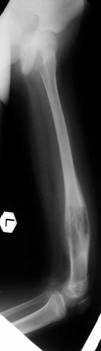

Post Op

Walks independently. Uses shoe raise.

ROM :0-125.LLD : 7cm

Plan : Left tibia lengthening